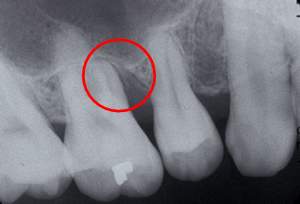

赤い部分が分岐部です。 最新の分岐部病変治療においてCT画像診断と、エルビウムヤグレーザー(歯や骨を削ることができる厚労省から認可されたレーザーです)を使用したエムドゲインによる再生療法で、かなり良い結果がでるようになりました。ただし、再生療法を成功させる上で、まず一番重要な事は『適応症・欠損形態を十分に吟味し診断する事』です。適応症を誤れば期待した再生の結果を得ることは出来ません。 |

| 42歳 男性 主訴 奥歯が腫れて咬むと痛い |

赤い部分の骨が破壊されています。 |